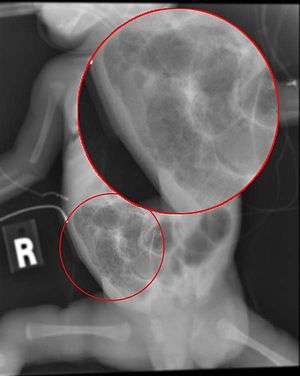

Radiograph of an infant with necrotizing enterocolitis | |

Necrotizing enterocolitis (NEC) is a medical condition primarily seen in premature infants,[1] where portions of the bowel undergo necrosis (tissue death). It occurs postnatally (i.e. it is not seen in stillborn infants)[2] and is the second most common cause of morbidity in premature infants,[3] causing 355 deaths per year in the United States in 2013, down from 484 in 2009. Rates per 100,000 live births were almost three times higher for blacks than for whites.[4]

The diagnosis is usually suspected clinically but often requires the aid of diagnostic imaging modalities, most commonly radiography. Specific radiographic signs of NEC are associated with specific Bell's stages of the disease:[2]

- Specific radiologic signs (pneumatosis intestinalis or portal venous air)

- Severe radiologic signs (pneumoperitoneum)